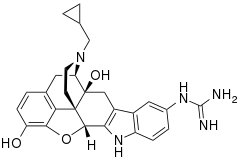

The pharmacodynamic response to an opioid depends upon the receptor to which it binds, its affinity for that receptor, and whether the opioid is an agonist or an antagonist. For example, the supraspinal analgesic properties of the opioid agonist morphine are mediated by activation of the μ1 receptor; respiratory depression and physical dependence by the μ2 receptor; and sedation and spinal analgesia by the κ receptor. Each group of opioid receptors elicits a distinct set of neurological responses, with the receptor subtypes (such as μ1 and μ2 for example) providing even more [measurably] specific responses. Unique to each opioid is its distinct binding affinity to the various classes of opioid receptors (e.g. the μ, κ, and δ opioid receptors are activated at different magnitudes according to the specific receptor binding affinities of the opioid). For example, the opiate alkaloid morphine exhibits high-affinity binding to the μ-opioid receptor, while ketazocine exhibits high affinity to ĸ receptors. It is this combinatorial mechanism that allows for such a wide class of opioids and molecular designs to exist, each with its own unique effect profile. Their individual molecular structure is also responsible for their different duration of action, whereby metabolic breakdown (such as N-dealkylation) is responsible for opioid metabolism.

A new strategy of drug development takes receptor signal transduction into consideration. This strategy strives to increase the activation of desirable signalling pathways while reducing the impact on undesirable pathways. This differential strategy has been given several names, including functional selectivity and biased agonism. The first opioid that was intentionally designed as a biased agonist and placed into clinical evaluation is the drug oliceridine. It displays analgesic activity and reduced adverse effects.[162]